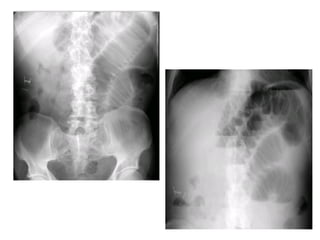

THUÛNG TAÏNG ROÃNG

* Vò trí

o Thöôøng ôû phaàn cao oáng tieâu hoaù (vieâm loeùt, nhieãm truøng,

thuûng do ngoaïi vaät nuoát vaøo…)

o Caùc oáng tieâu hoaù tröôùc coät soáng (chaán thöông)

* Daáu hieäu kinh ñieån: lieàm hôi döôùi hoaønh: xuaát hieän 6-8

giôø sau thuûng vôùi löôïng hôi khoaûng 20-50ml

* Caùc tö theá khaùc: BN nghieâng (T) laáy heát bôø ngoaøi gan vaø